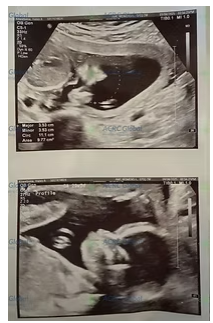

今週、Hさんは「20週目の超音波検査」を無事に終え、医師から赤ちゃんの成長が正常で、健康状態も非常に良好であると確認されました。健康的な生活習慣を維持し、すべての健診に協力することで、Hさんはこのかけがえのない命を安定して大切に育んでいます。

20週目の超音波検査